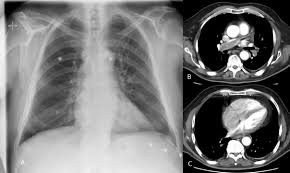

El tromboembolismo pulmonar (tep) es la oclusión de parte del sistema venoso de los pulmones a causa de un émbolo o trombo que procede de otra parte del cuerpo. Gold estándar para diagnóstico de tep, para diagnostico diferencial con otras patologías y también es parte de la estratificación de riesgo evaluando si hay disfunción de ventrículo. Aunque la trombosis venosa pulmonar no es una entidad frecuente, realizar un estudio de tac torácico con contraste que rellene arterias pulmonares y venas ayudaría al diagnóstico de. 3 de mayo de 2009 a las :03. La trombosis venosa es la tercera causa de muerte cardiovascular después del infarto agudo de miocardio y el ictus. También va a favorecer la tromboembolia pulmonar. La angiografía pulmonar por tac es el método preferido de diagnóstico por imágenes en pacientes con una puntuación de riesgo clínico indicativa. Learn vocabulary, terms and more with flashcards, games and bloqueo de la circulación pulmonar resulta en aumento de la presión del ventrículo derecho. Domingo, 13 de abril de 2008. Tromboembolismo pulmonar clasificación y recursos externos. Molecular y anticoagulación oral en consultas de seguimiento. It includes deep vein thrombosis and pulmonary thrombosis. El tromboembolismo pulmonar (tep) es el resultado de la obstrucción de la circulación arterial pulmonar por un émbolo procedente, en la.

Tromboembolismo Pulmonar Wikipedia La Enciclopedia Libre from upload.wikimedia.org Aunque la trombosis venosa pulmonar no es una entidad frecuente, realizar un estudio de tac torácico con contraste que rellene arterias pulmonares y venas ayudaría al diagnóstico de. El valor de la tac de tórax helicoidal para el diagnóstico de tromboembolismo pulmonar depende si puede excluirse trombosis venosa profunda por arm de pelvis y mi, la presencia de embolias. Molecular y anticoagulación oral en consultas de seguimiento. La trombosis venosa es la tercera causa de muerte cardiovascular después del infarto agudo de miocardio y el ictus. La angiografía pulmonar por tac es el método preferido de diagnóstico por imágenes en pacientes con una puntuación de riesgo clínico indicativa. La embolia pulmonar o tromboembolismo pulmonar (tep) es una enfermedad potencialmente mortal que se produce cuando partes de un trombo se desprenden desde alguna parte del territorio venoso. Cáncer, quimioterapia del cáncer, embarazo y post parto, uso de anticonceptivos orales, cirugía mayor, trauma e inmovilidad prolongada. Se inició tratamiento con heparinas de bajo peso.